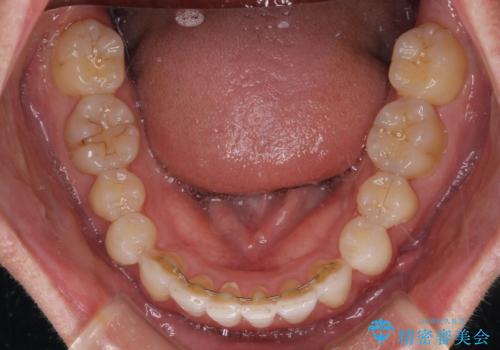

- 前歯のデコボコを治したいとのことで来院された患者様です。

上下顎ともに歯列全体の後方移動とIPR(歯と歯の間を削る)によってデコボコが解消するように設計し、インビザラインにより治療を行うこととしました。

矯正治療後、前歯の形と色が気になるとのことでしたが、大分前に失活している(神経が取り除かれている)歯であり、その影響で変色しているため、オールセラミッククラウンによる補綴治療をおすすめいたしました。